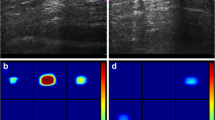

A false negative at mammography was shown to be a true positive at DeHCA optical image processing (score 0.85) (Fig. 13). With US, a hypoechoic nodule was observed in the outer quadrant of the left breast with irregular borders of 12 × 6 mm with calcifications inside (Fig. 14). Mammography showed a heterogeneous hyperdense lesion with irregular borders of approximately 30 cm in diameter. DeHCA optical image processing gave a true positive result (score 0.92).

Mammography (a) shows a heterogeneous finding with irregular edges of approximately 30 cm in diameter. DeHCA score (b) was equal to 0.92. At US (c), in the outer quadrant of the left breast, a hypoechoic nodule with irregular borders is visible, measuring 12 × 6 mm, with internal dot-like calcifications. Final diagnosis: invasive ductal carcinoma